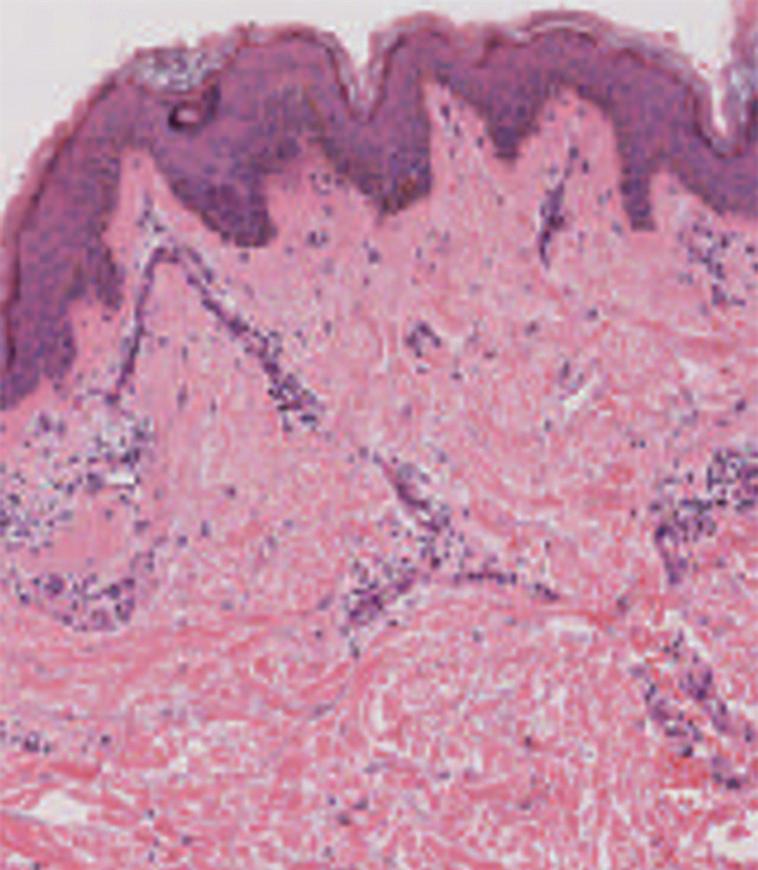

Figura 1.1 (A e B) Pele: esquema das camadas cutâneas (A) e da pele normal (hematoxilina e eosina [HE]) (B)

Figura 1.6 Pele apresentando cones epiteliais e papilas dérmicas (hematoxilina e eosina [HE])